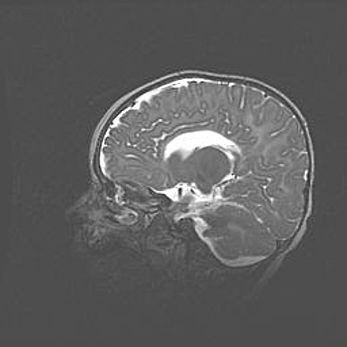

Открытая гидроцефалия.

Возраст: 6 месяцев 15 дней

Вес: 6200 г

Пол: женский

Окружность головы: 41 см

Срок гестации: 38 недель

Гидроцефалия головного мозга у новорожденных – это скопление избыточного количества цереброспинальной жидкости в головном мозге. Ее избыточное скопление в мозге приводит к патологическому расширению желудочков мозга (четырех полостей, расположенных в глубине белого вещества мозга, заполненных цереброспинальной жидкостью и связанных узкими проходами).

Открытый тип гидроцефалии (сообщающаяся) наблюдается тогда, когда нарушен механизм всасывания ликвора в системный кровоток. При этом типе причиной заболевания чаще всего является перенесенные ранее инфекции (например: менингит),  либо же наличие крови в субарахноидальном пространстве.